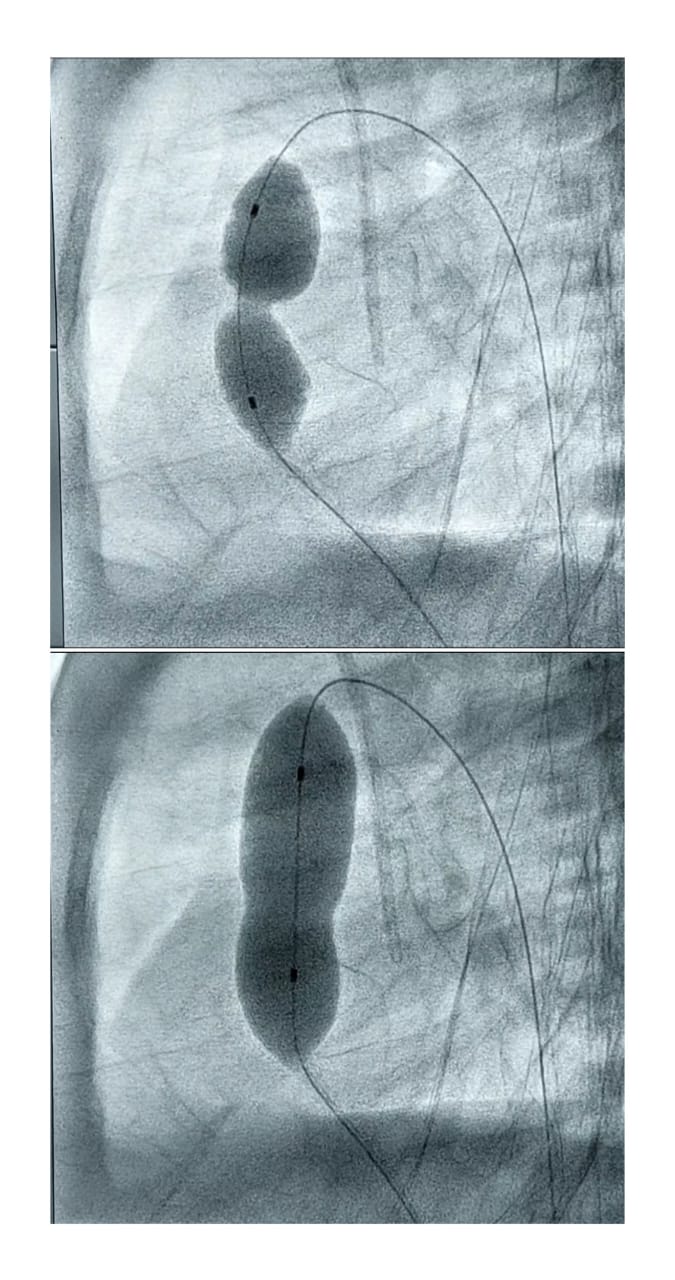

لعلاج حالة شديدة الخطورة لطفل حديث الولادة يعاني من ضيق شديد خلقي بالشريان الرئوي وانخفاض مستوى الأكسجين بالدم تم حجز الطفل بالحضان ثم دخوله قسطرة القلب وتم توسيع الصمام الرئوي بالبالون وخروج الطفل للحضان

وتعتبر هذه الحالة هي أصغر سن لحالة يتم إجراء تدخل علاجي لها عن طريق القسطرة